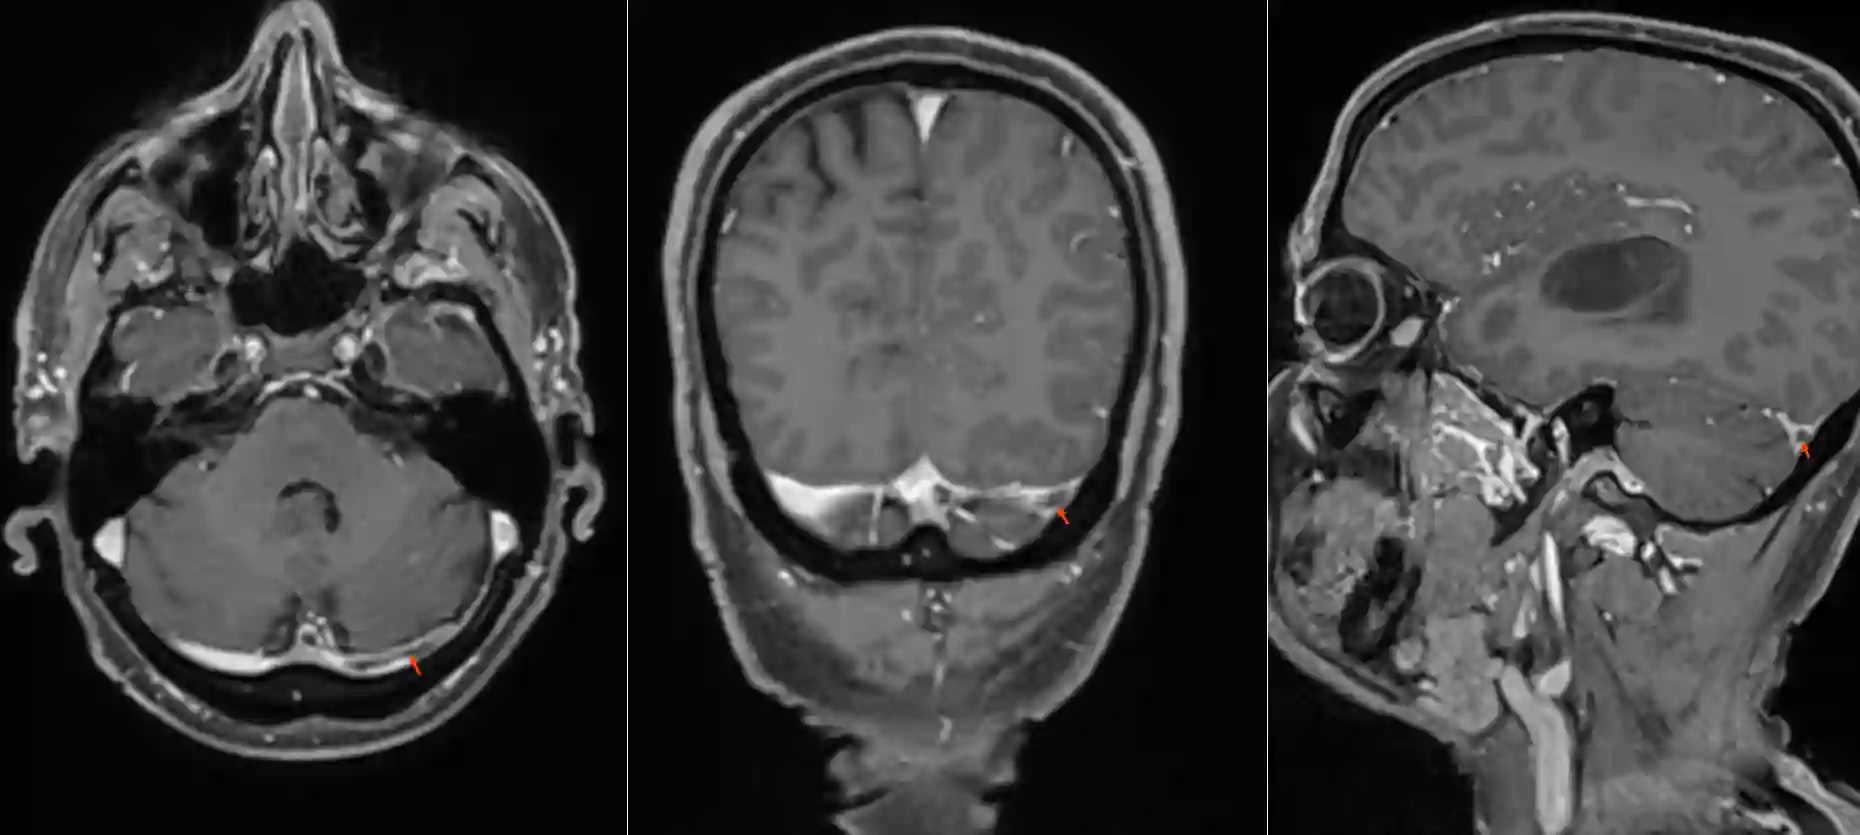

Bildgebung

Sinusvenenthrombosen können je nach Ausprägung des Thrombos in einer CT, MRI Bildgebung als auch einer digitalen Subtraktionsangiographie visualisiert werden.